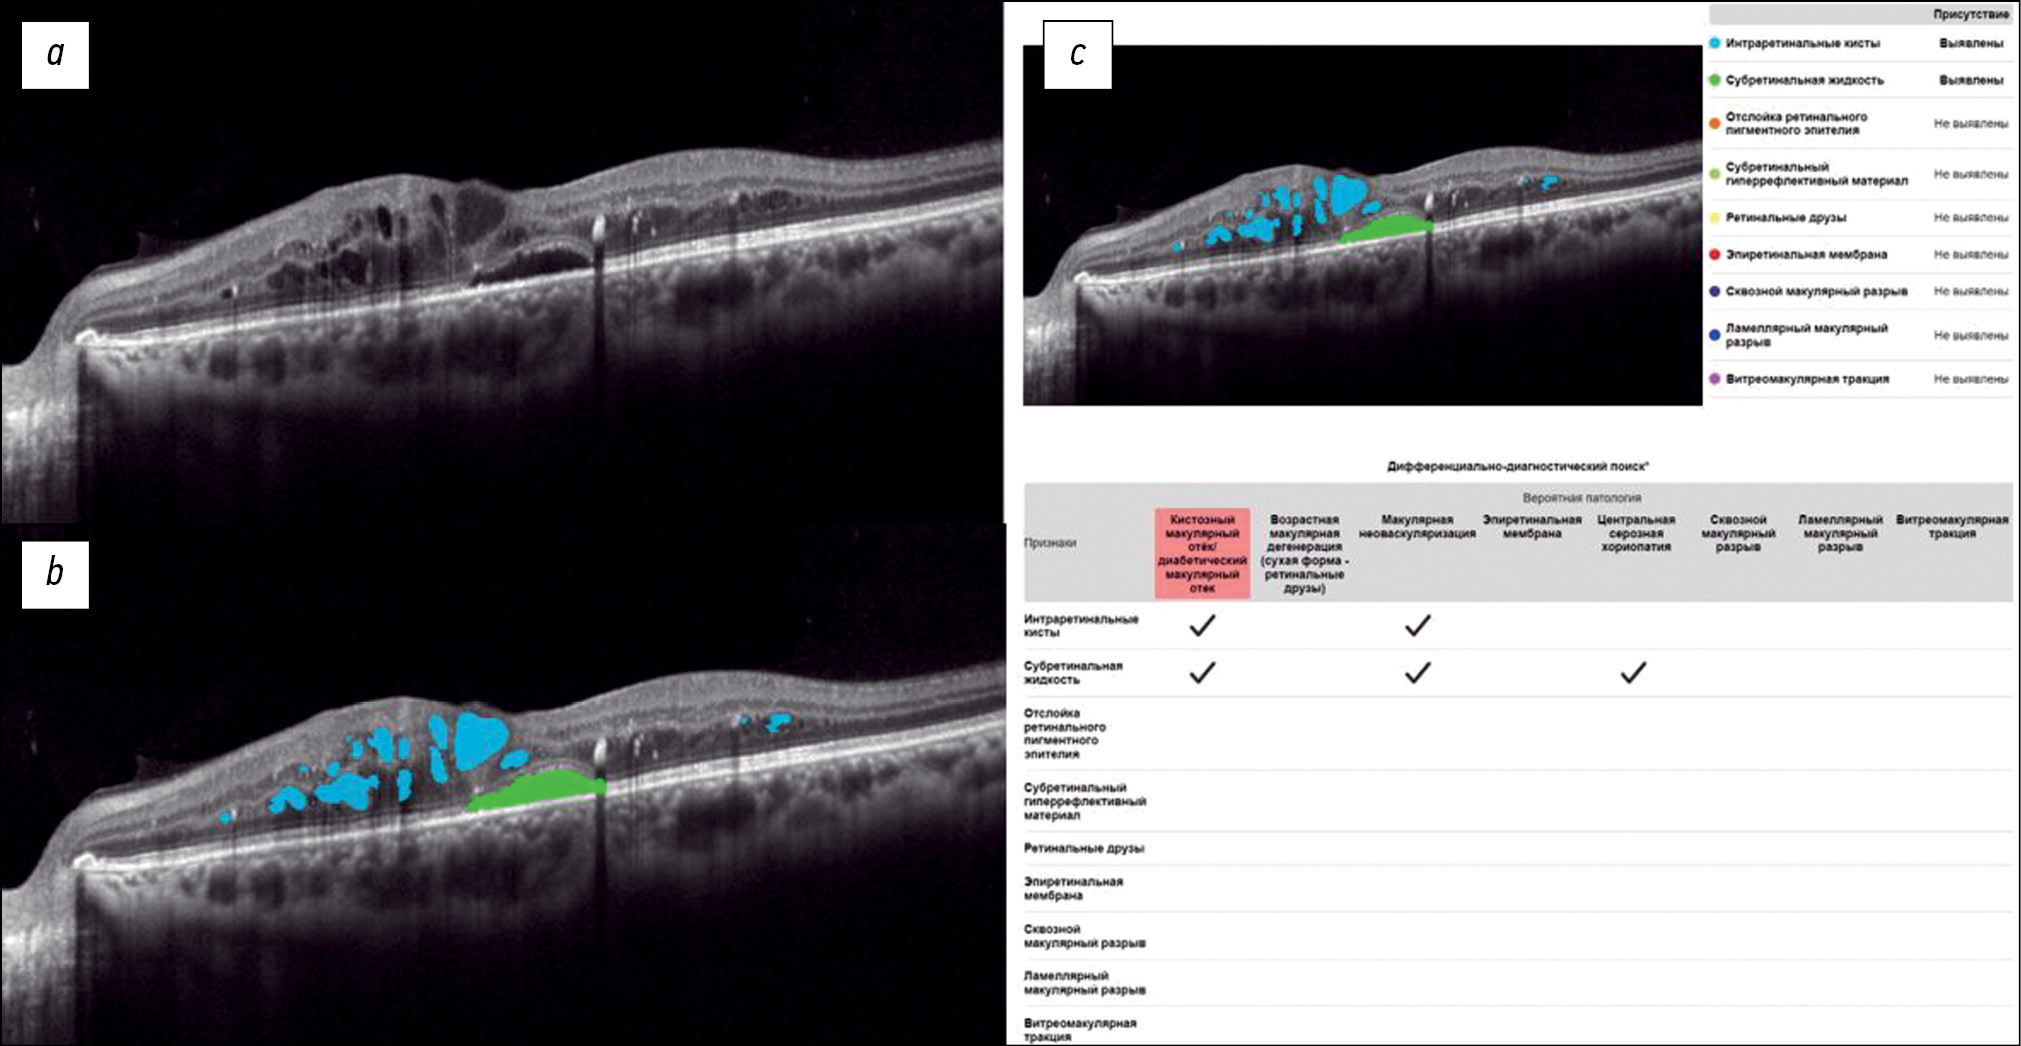

Fig. 1 shows a structural OCT scan of the macular zone of patient B (54 years old) with type 2 diabetes mellitus. The ophthalmologist’s report recorded DME. In the analysis of the structural OCT scan by Retina.AI, the algorithms segmented the following pathological signs: intraretinal cysts, subretinal fluid. In conclusion, the patient was diagnosed with DME.

Fig. 1. An example of the optical coherence tomography scan analysis of a patient with diabetic macular edema by the artificial intelligence algorithm: a — structural optical coherence tomography scan; b — optical coherence tomography scan after segmentation of the pathological features (subretinal fluid — green mask, intraretinal cysts — blue masks); c — scan analysis report (the reporting table of the differential diagnostic search, probable pathology is highlighted in red — macular edema).